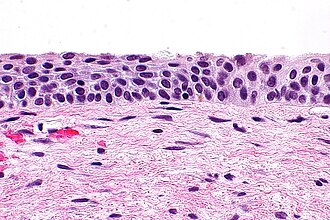

Uterine cervix with atrophic changes

Uterine cervix with atrophic changes is relatively common and is important to recognize as it can mimic HSIL.

Atrophic cervix. H&E stain.

LM small squamous cells with grey/blue cytoplasm, no "dancing"/"sparkling" chromatin, no mitoses

LM DDx HSIL, immature squamous metaplasia

Features - squamous cells:

• Cells smaller.

• Cytoplasm grey/blue.

• No "dancing"/"sparkling" chromatin.

• No mitoses.